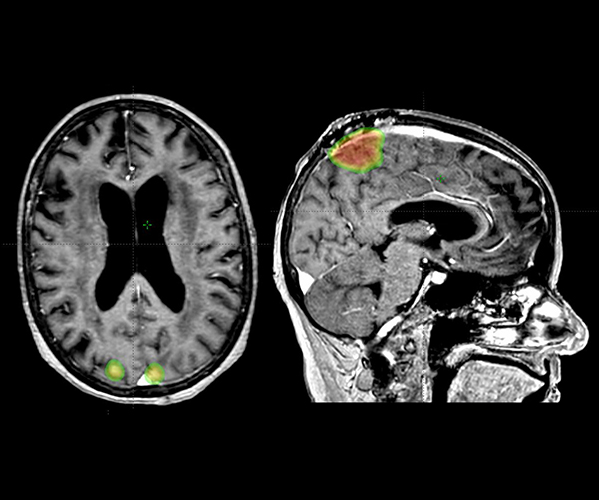

SRS is a form of external beam radiation that delivers high doses of radiation to very small volumes within the brain. SRS is typically given in a single day, but can be delivered over three to five days for larger, more complex tumors. Prior to the development of SRS, many brain tumors were treated with large volumes of radiation covering the entire brain. With SRS, less of the brain is exposed to radiation, resulting in more limited side effects. Additionally, SRS is able to deliver higher doses of radiation to the target than is possible with whole brain radiation, resulting in better outcomes. SRS is typically used to treat cancers that have metastasized to the brain, but is also used for non-cancerous growths such as meningiomas, pituitary adenomas, arteriovenous malformations, and vestibular schwannomas.